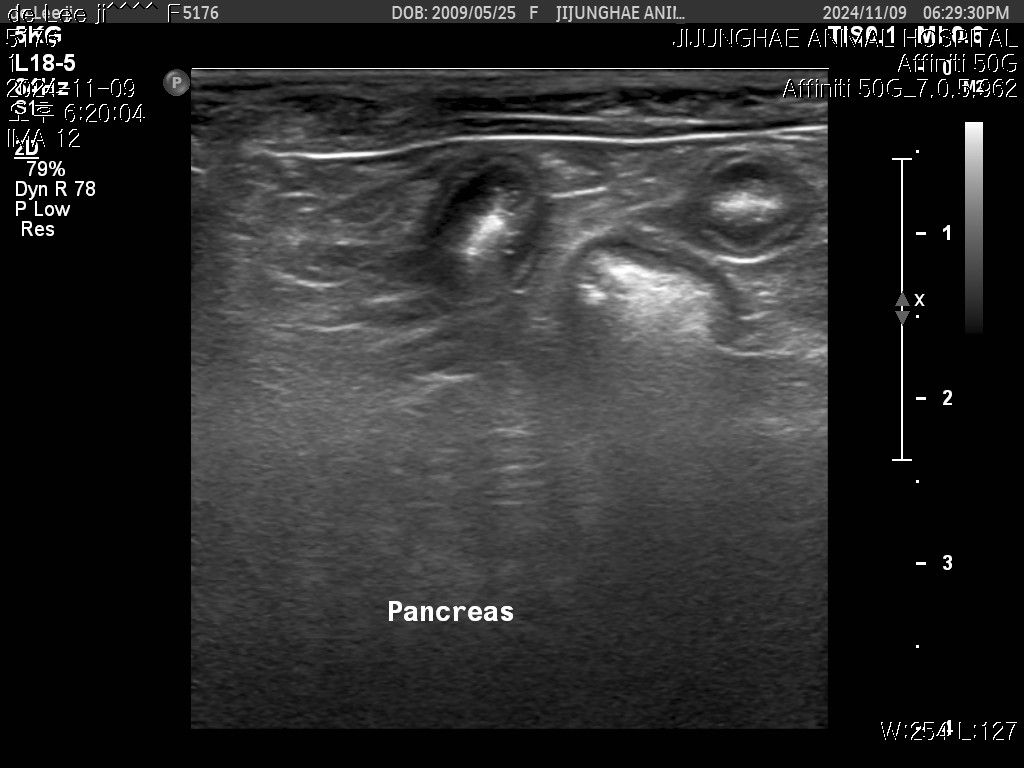

작년 검진때도 듣긴했는데 올해 다시 초음파를보니

키위모양으로 있던데..찾아보니 키위모양이 많이위험하다고들었습니다

초음파사진 같이첨부하니 아이의 점액종 상태가

어떤지좀 봐주세요 제발부탁드립니다 !!!🙏